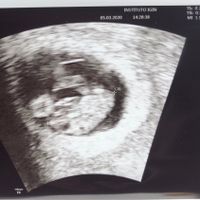

Hola chicas, Estoy en la semana 31 de embarazo y han diagnosticado a mi bebé como CIR (p3) y han visto que tengo las arterias uterinas patológicas. Ahora controles semanales para ir comprobando que él...